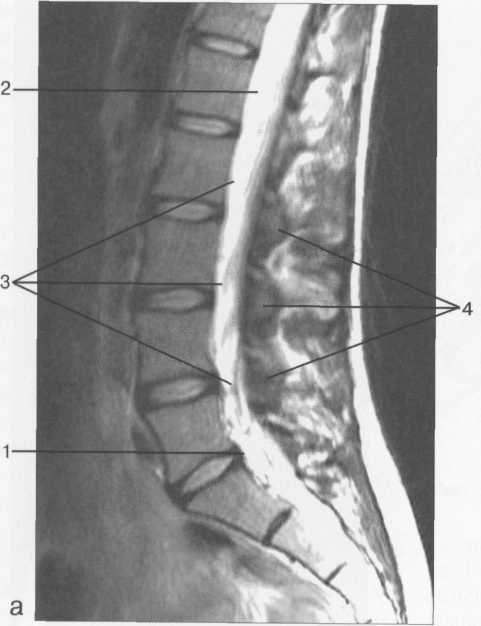

МРТ исследования дают широкую возможность исследовать  все структуры спинного мозга в разных плоскостях. ( рис. 37-41 )

Рис. 37. Срединные сагиттальные МРТ пояснично-крестцового отдела позвоночника.

а-Т2-ВИ;б-Т1-ВИ.

1 -- конус спинного мозга; 2 -- конский хвост спинного мозга; 3 -- субарахноидальное пространство; 4 -- дуральный мешок; 5 -- терминальная нить; 6 -- эпидуральное пространство; 7 -- тело Sp 8 -- пуль­позное ядро межпозвонкового диска; 9 -- фиброзное кольцо межпозвонкового диска; 10 -- каналы бази-вертебральных вен; 11 -- остистый отросток LIV.